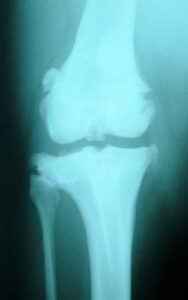

- Labrador Retriever, Maschio, 7 anni

• grave HD (peggiore sul lato destro)

• cronica parziale rottura del CrCL sn = grave OA

• artroscopia = parziale meniscectomia

• 41.6 Kg, BCS 6/9

Fisioterapia:

- NO DOLORE, < infiammazione

- > ROM, > massa muscolare

- ricoverato dal 4 al 25 Agosto

- 4 passeggiate al giorno

- Diatermia + es PROM + UWTM – BID

- dieta: Hill’s j/d Restricted

• più contento, vuole giocare e correre

• vuole andare in passeggiata e lo dimostra

• urina su 3 zampe (2 anni che non lo faceva)

• miglior ROM articolare